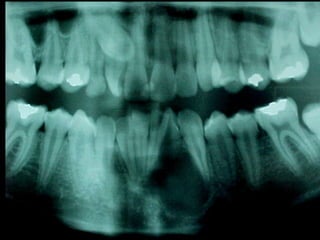

La periodontitis, denominada comúnmente piorrea, es una enfermedad que

inicialmente puede cursar con gingivitis, para luego proseguir con una pérdida de

inserción colágena, recesión gingival, e incluso la pérdida de hueso, en el caso de

no ser tratada, dejar sin soporte óseo al diente. La pérdida de dicho soporte

implica la pérdida irreparable del diente mismo.

De etiología bacteriana que afecta al periodonto (el tejido de sostén de los dientes,

constituido por la encía, el hueso alveolar, el cemento radicular y el ligamento

periodontal) se manifiesta más comúnmente en adultos mayores de 35 años, pero

puede iniciarse en edades más tempranas.

Periodontitis

Una periodontitis según su grado de afectación dental se clasifica en: leve,

moderada o grave. Y según su extensión se denomina: localizada o

generalizada.

Las periodontitis desde 1999 se han clasificado (ASP) en: crónicas,

agresivas y asociada a estados sistémicos.